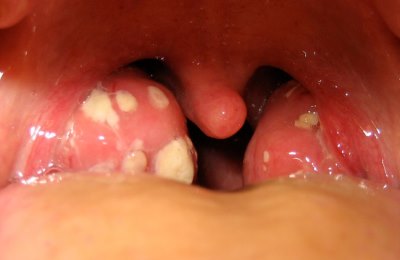

Полоскание горла содой особенно эффективно при ларингитах, ангинах и стоматитах. Эта лечебная процедура поможет быстро снять боли, убрать гнойный налет с миндалин, уменьшить воспаление слизистой.

На начальной стадии болезни (особенно при наличии гнойных пробок на миндалинах) споласкивание носоглотки можно проводить до 5-ти раз в сутки.